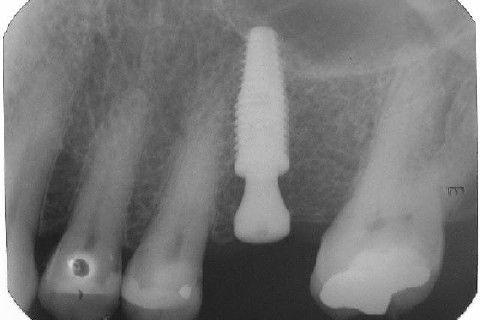

Instalação de um implante em região do 26. Utilizamos um implante cone morse Alvim Neodent 4.3 X 11,5. Foi uma cirurgia muito rápída e minimamente traumática, sem retalho e sutura.